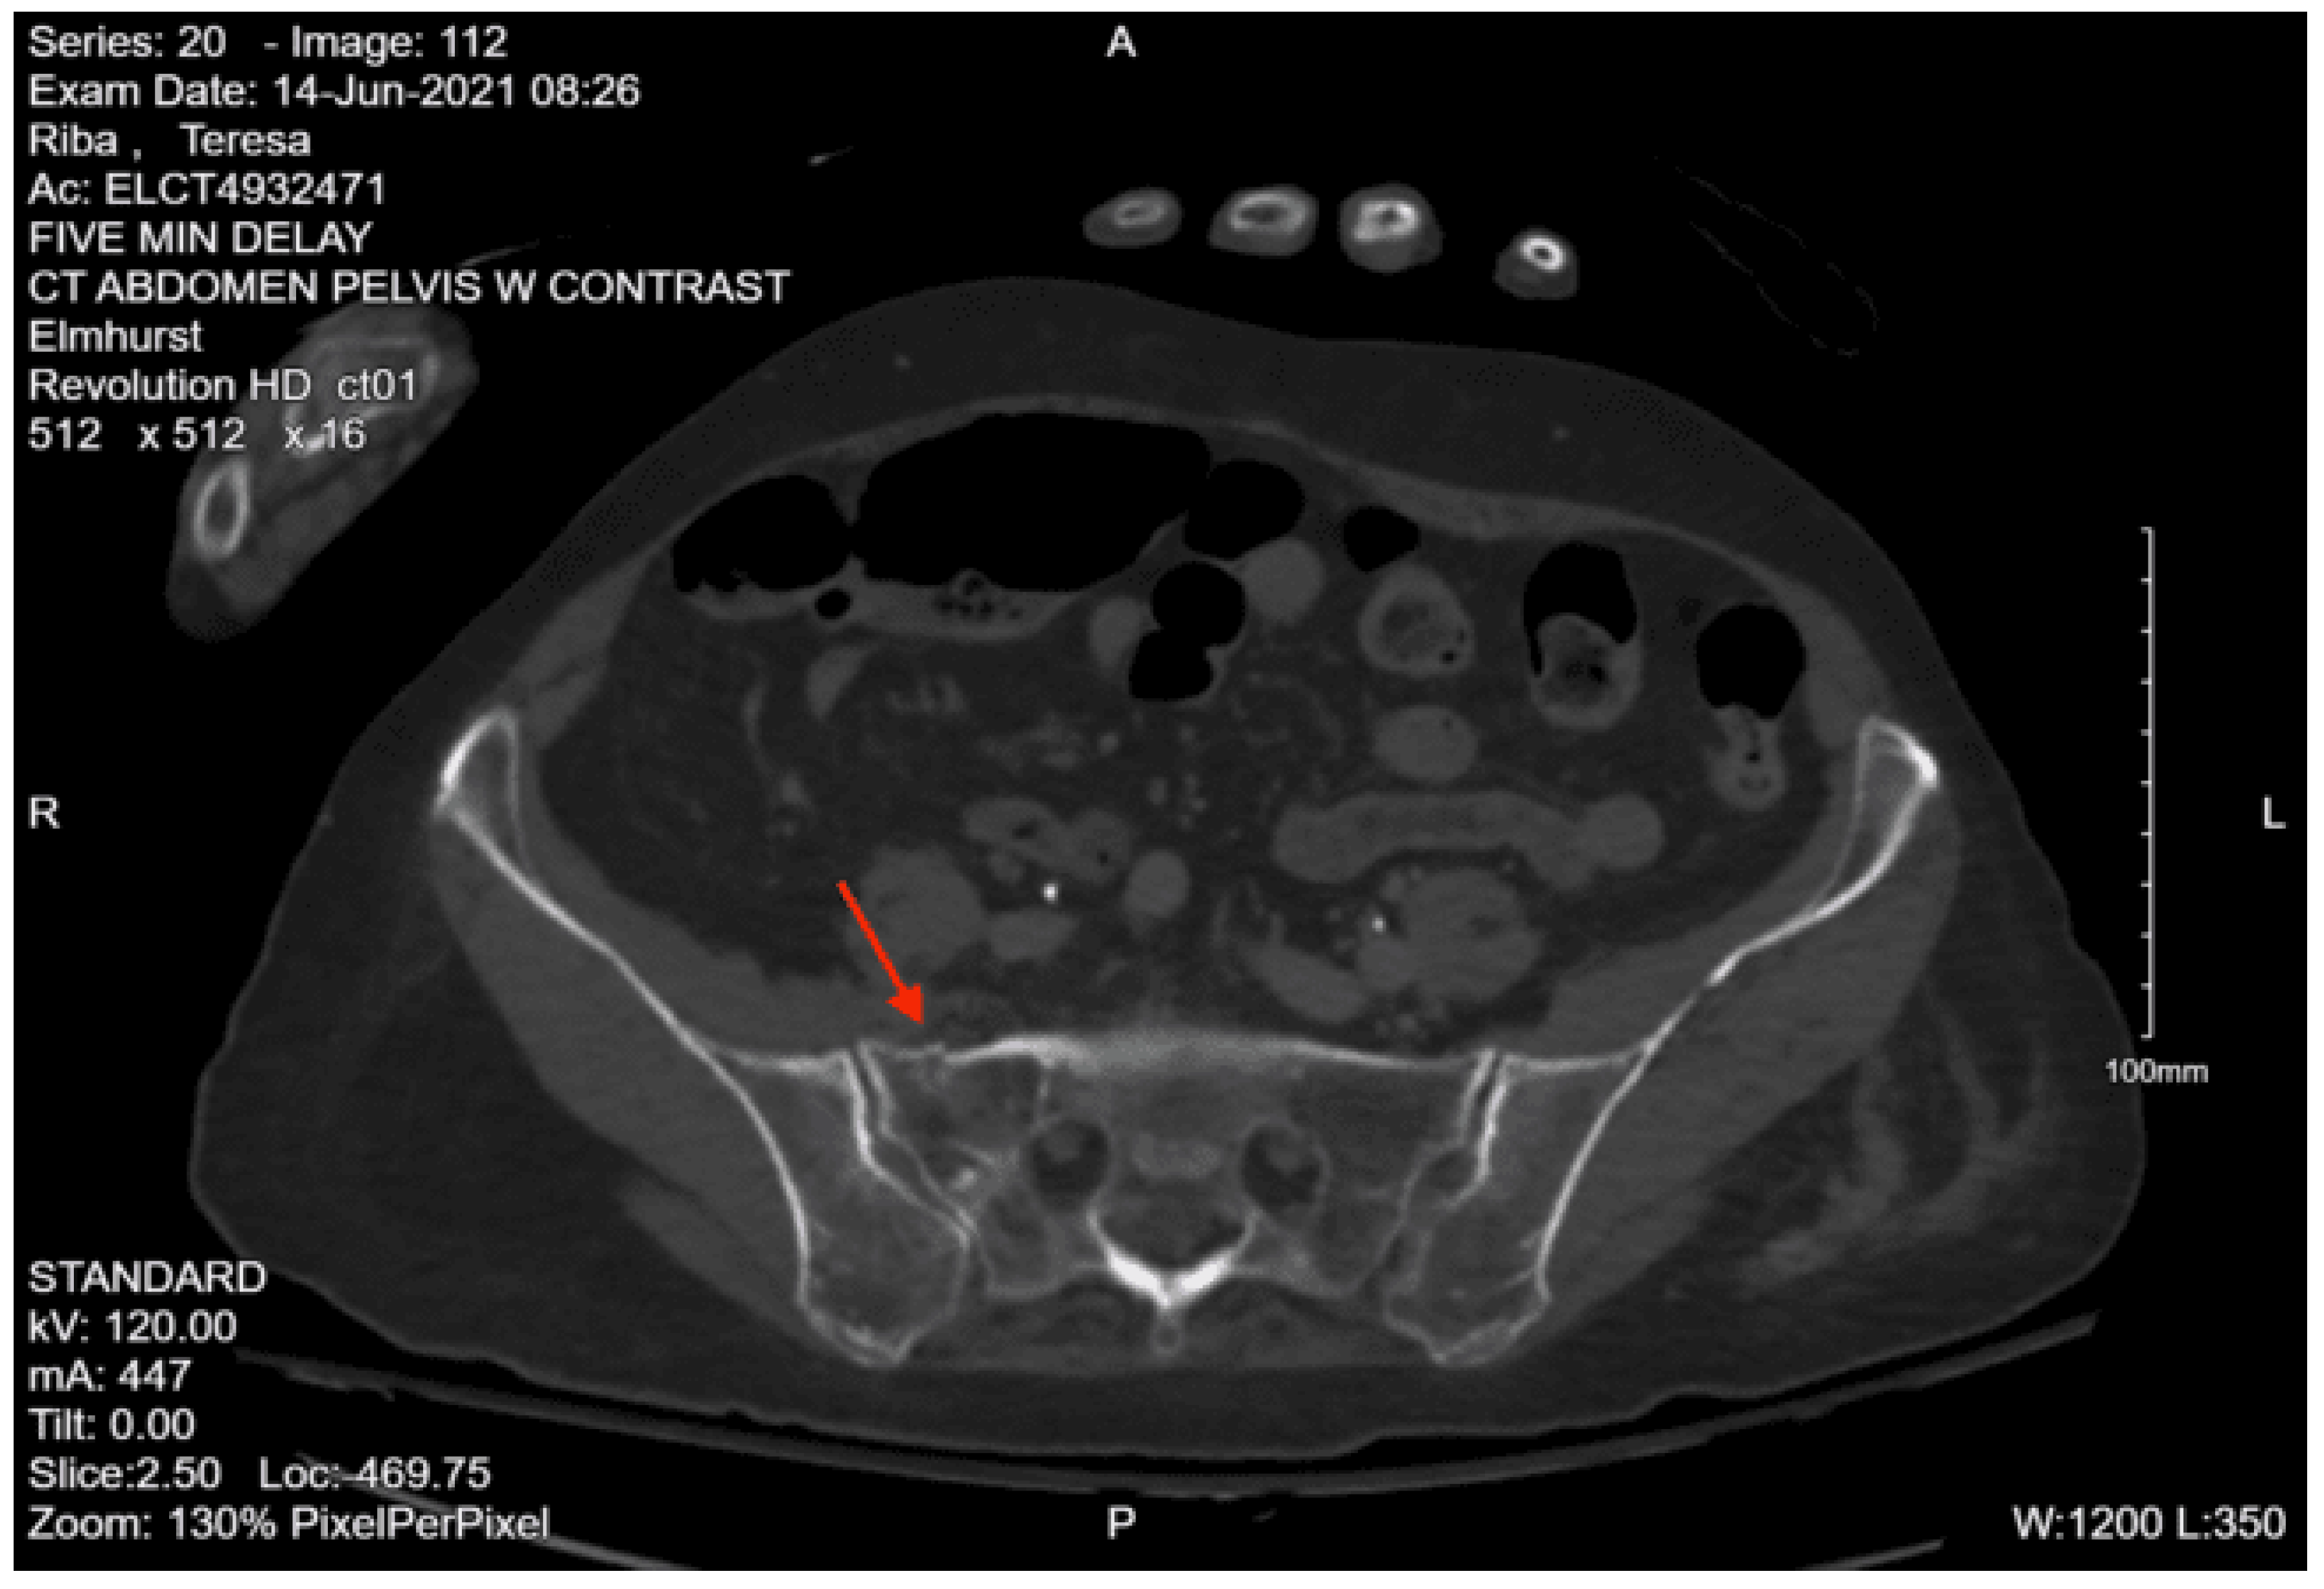

Imaging as shown in Figure 24, Figure 25 and Figure 26:

CT abdomen pelvis with contrast: Grossly intact abdominal and pelvic viscera with acute fracture of the left superior pubic ramus near the symphysis and the bilateral inferior pubic rami.

CT lumbar spine without contrast: Diffuse osteopenia of the lumbar spine with suggestion of a fracture involving the anterior aspect of the vertebral body of L5 in its superior portion and acute fracture of the anterior aspect involving the lateral mass of S1